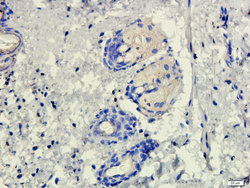

- Submitted by

- antibodies-online (provider)

- Main image

- Experimental details

- IHC